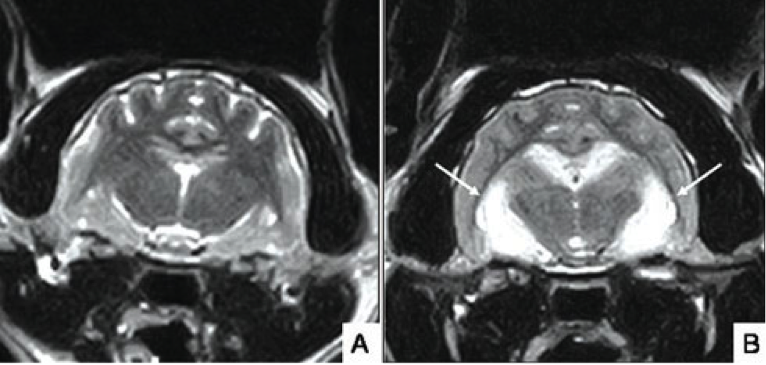

[Изображение А – МРТ головного мозга здорового кота. Изображение В – МРТ головного мозга кота с подозрением на эпилепсию, вызванную повреждением головного мозга (гиппокампа некроза) [Белые стрелки]. Пациент подвержен острым генерализованным приступам, которым присущи поведенческие изменения (агрессия, слюнотечение, дезориентация).